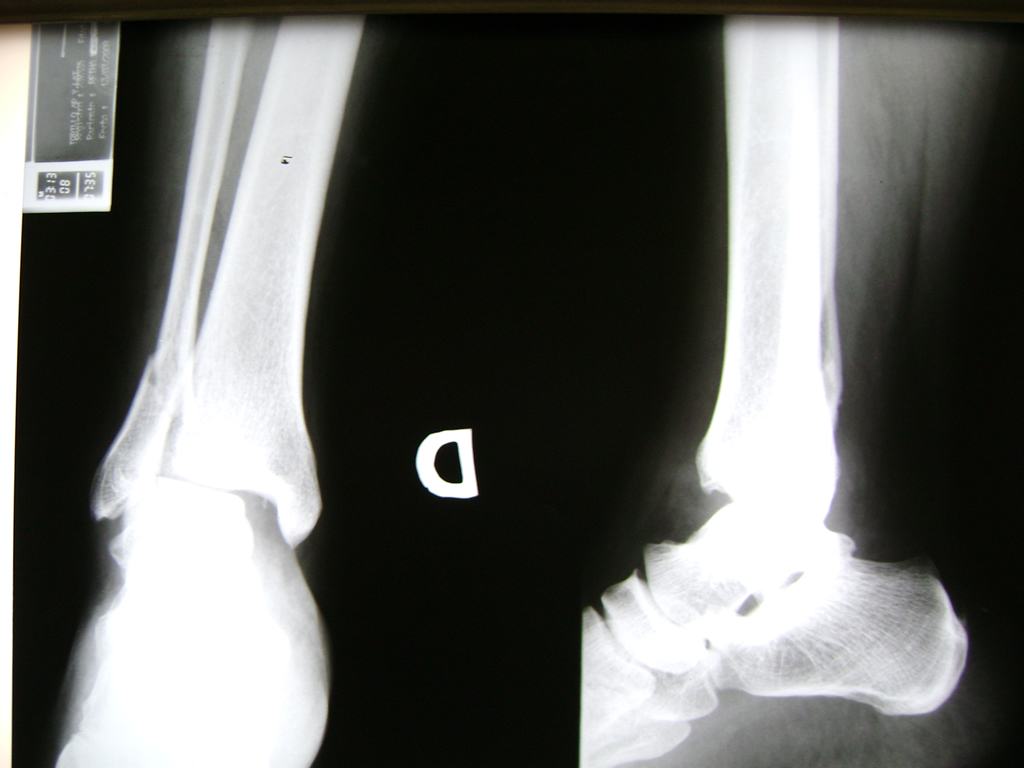

Algunas fracturas de tobillo pueden requerir cirugía si:

- Los extremos de los huesos están desalineados entre sí (desplazados).

- La fractura se extiende hasta la articulación del tobillo (fractura intra-articular).

- Los tendones o ligamentos (tejidos que sujetan los músculos y los huesos entre sí) están rotos.

- El médico cree que sus huesos probablemente no sanen apropiadamente sin cirugía.

- El médico considera que la cirugía puede permitirle una recuperación más rápida y confiable.